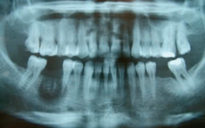

Gây mê trong điều trị nha cho các bệnh nhân đặc biệt để tối ưu kết quả điều trị

ẢNH: BÁC SĨ CUNG CẤP